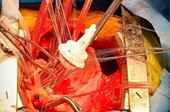

Dr.DineshShanmugaSundaram is specialized himself in each & every part of Cardiovascular & Thoracic Surgery both in Adult & Paediatric or Congenital Heart Diseases. He is both an ethical & academic surgeon,changed the trend in Cardiac Surgery to fast & safe level, as prolonged procedures in Cardiac Surgery increases postoperative complications. We aim at decreasing perioperative complications to the maximal level. Read More